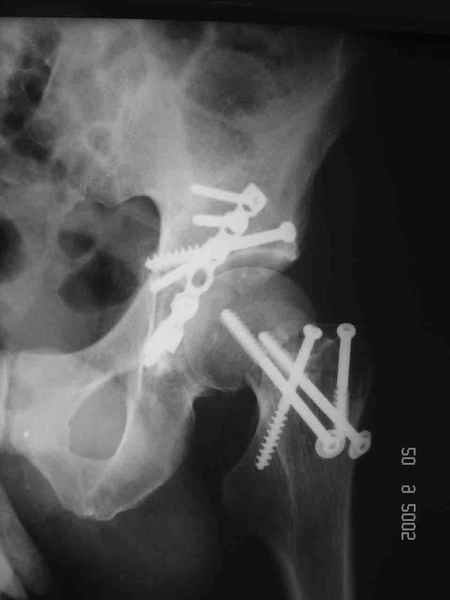

Уважаемые коллеги. Больной был оперирован в одну сессию 25 августа. Сначала на голень наложен спице-стержнвой аппарат. Затем выполнен остеосинтез вертлужной впадины Y-образным доступом. Пришлось дополнительно отсекать вертел. Шейка синтезирована спонгиозными винтами и спицами, вертел - спицами и стягивающей петлей. После операции находился на вытяжении 3 нед. Раны зажили первичным натяжением. Сейчас уже дома. Будет и дальше без нагрузки на левую ногу. Будем наблюдать в динамике. Ждем комментарии.

Обычно мы поступаем так же, однако в этом случае имелся дефект верхней части шейкии, перелом и остеотомия вертельной области, так же с дефектами, спицы - вынужденная мера. Здесь ведь пучок спиц не вместо трех винтов, а в дополнние к двум. Эти-то два пришлось провести чуть ли не с уровня диафиза, проксимальнее было сплошное крошево.

Перелом шейки был многооскольчатйй очень медиальный, по сути шейку и вертел расколотило об подвздошную кость с кучей мелких фрагментов, вертел был полностьб вовлечен в перелом, головка заподлицо скрывалась в расширенной вертлужной впадине. Качество кости приличное. Остатки дуги Адамса с предварительно проведенными винтами я вколотил в головку и компрессировал винтами - оказалось прочно, но образовался дефект верхнего отдела шейки, который был заплнен фрагментами фиксироваными трансфрактурными спицами - отсюда пучек.

Вертел во время доступа пришлось еще рубить, т.к.

переломы распространялись чересчур дистально.

Отсюда еще пучек спиц.